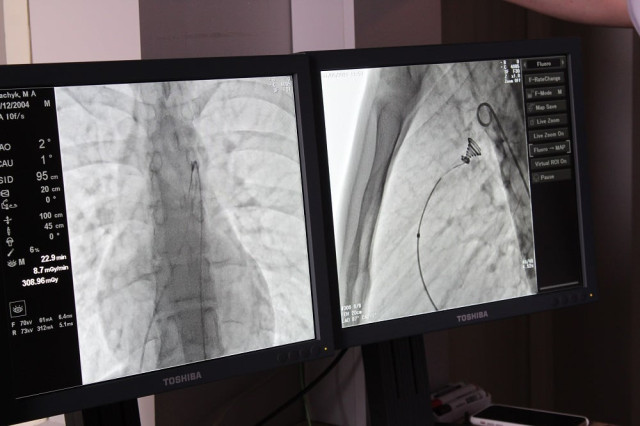

Вона була складною і проводилась під рентгенівським контролем із застосуванням ангіографа, під місцевим знечуленням (без наркозу). Через прокол у стегновій вені і артерії в незакриту протоку встановлено оклюдер (маленьку пружинку), яка перекрила потрапляння артеріальної крові у венозне русло.